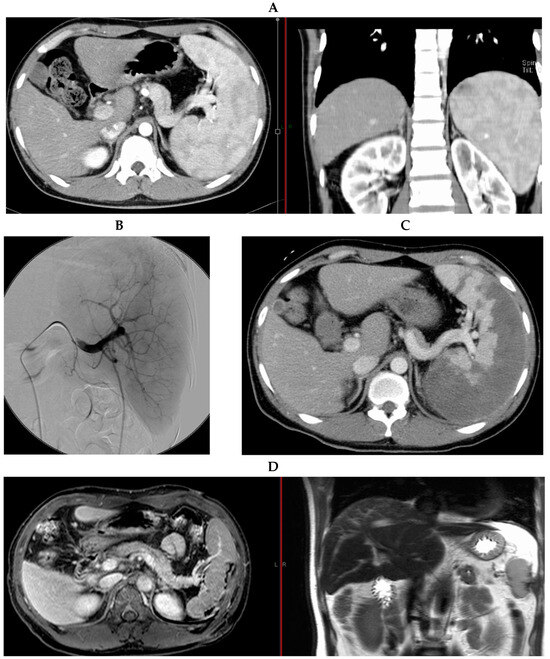

Partial Splenic Embolization in a Patient with Hemophilia A and Severe Thrombocytopenia: A Case Report

2. Case Report